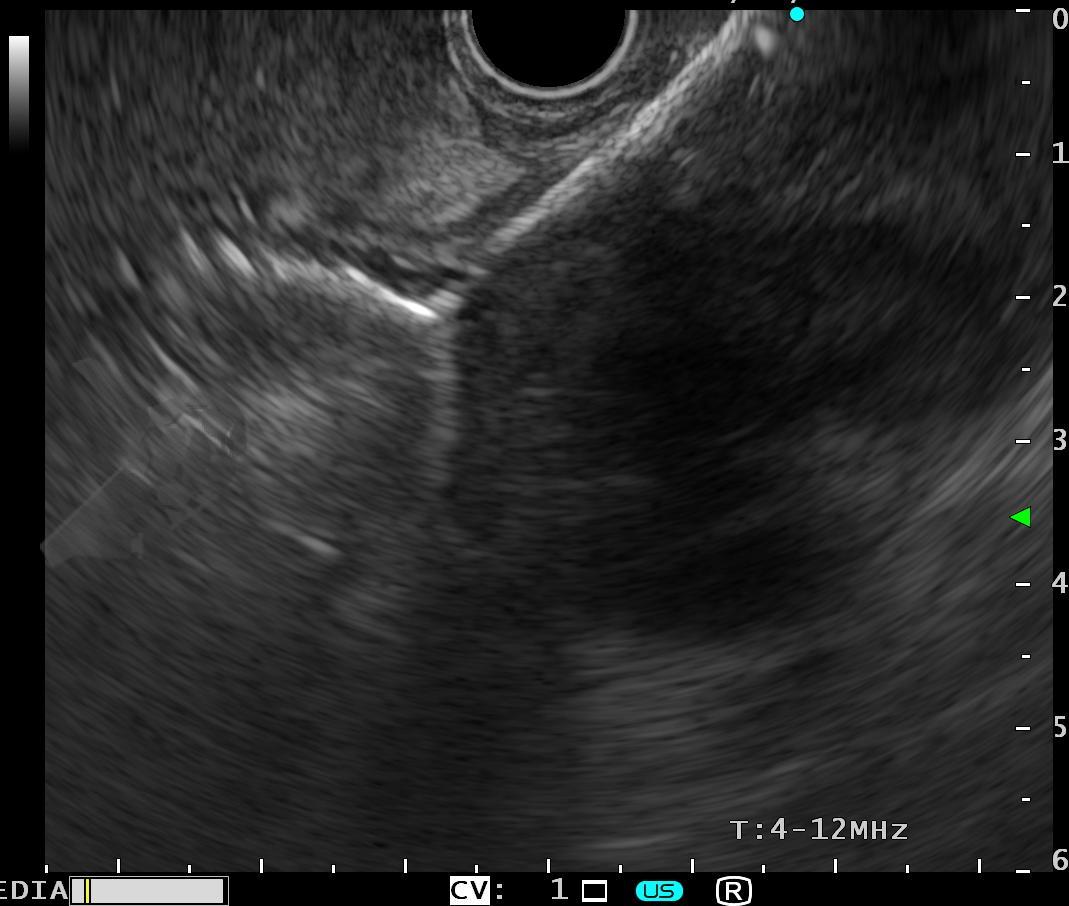

O principal método de drenagem biliar para obstruções malignas distais é a CPRE. Nos casos de impossibilidade/falha, a coledocoduodenostomia ecoguiada (EUS-choledoduodenostomy – CDS) surge como uma das principais opções, porém pode ser desafiadora devido fatores anatômicos, como colédoco < 12 mm, posição do colédoco distante do probe, além da possibilidade de disfunção do stent a longo prazo (1 – 3). Considerando um ducto cístico patente, a drenagem ecoguiada da vesícula (EUS-gallblader drainage – GBD) é uma alternativa interessante, pela técnica em geral mais fácil (alvo/vesícula de maiores proporções). Uma vez que os resultados são bons (100% de sucesso técnico e 10,8% de eventos adversos em um estudo), os autores optaram por investigar estas opções como primeira linha na paliação endoscópica da obstrução maligna distal (4, 5).

Trata-se de um estudo retrospectivo multicêntrico que incluiu casos de EUS-CDS e GBD como tratamento de primeira linha para drenagem biliar (sem tentativa de drenagem por CPRE). Foram incluídos pacientes com ducto cístico patente (avaliação prévia por RNM e/ou TC e durante a ecoendoscopia terapêutica), ambos métodos factíveis no procedimento inicial, colédoco > 12 mm e não candidatos a cirurgia.

A hot AXIOS foi utilizada em 87% dos casos de EUS-GBD e 92% das CDS. Nos demais casos, a hot Spaxus foi o stent empregado.

Os guidelines atuais recomendam a drenagem ecoguiada ao invés da percutânea para falha da CPRE em casos de obstrução biliar distal maligna (1, 6). A EUS-CDS pode ser tecnicamente desafiadora ou até inviável por uma dilatação biliar discreta e/ou distância do probe para o colédoco. Assim, a EUS-GBD apresenta-se como opção factível quando o ducto cístico é patente e não há histórico de colecistectomia.

Os resultados para os entusiastas das drenagens ecoguiadas são muito positivos: 96% de sucesso técnico, 86% de sucesso clínico e 11% de eventos adversos, todos sem diferença estatística quando comparados a EUS-CDS. Vale lembrar que estudos prévios já nos fornecem evidência para empregar a EUS-CDS no tratamento da estenose biliar maligna distal mesmo sem tentar realizar a CPRE (7). Quando comparada à CDS, a GBD apresenta a vantagem de ser tecnicamente mais fácil, podendo ainda, ser factível com maior frequência.

Outro ponto que deve ser sempre mantido em mente para a GBD é a necessidade de uma boa avaliação da patência do ducto cístico tanto por exame de imagem seccional prévio (RNM e/ou TC) e na ecoendoscopia terapêutica.